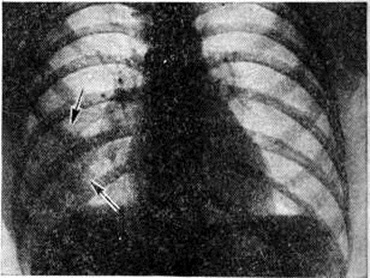

При очаговой Пневмония умеренный лейкоцитоз отмечается лишь у половины больных. Более характерны нейтрофильный сдвиг влево, ускоренная РОЭ, уменьшение или исчезновение эозинофилов. При выраженных явлениях интоксикации может наблюдаться протеинурия, микрогематурия и цилиндрурия. У больных с очаговой Пневмония снижены жизненная ёмкость лёгких и максимальная вентиляция, повышены минутный объем дыхания, отношение остаточного объёма к общей ёмкости лёгких. У 23% больных отсутствуют убедительные клинические, признаки очаговой Пневмония, и диагноз ставят на основании рентгенологическое данных.